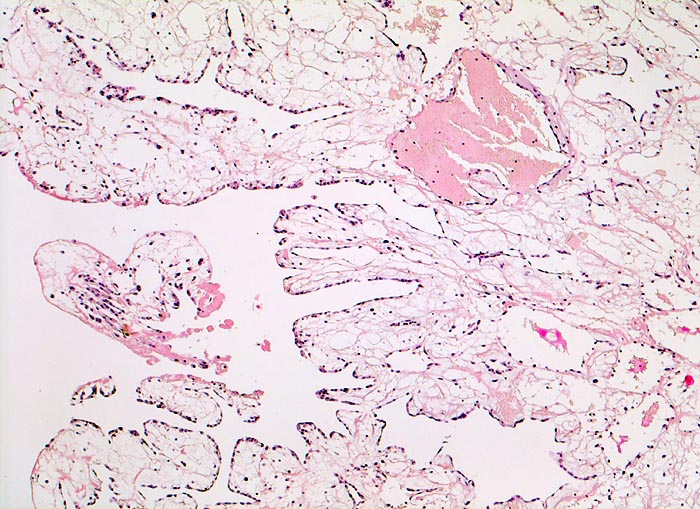

Vorhofmyxom

Makroskopie

Befund

Pathologischer Befund